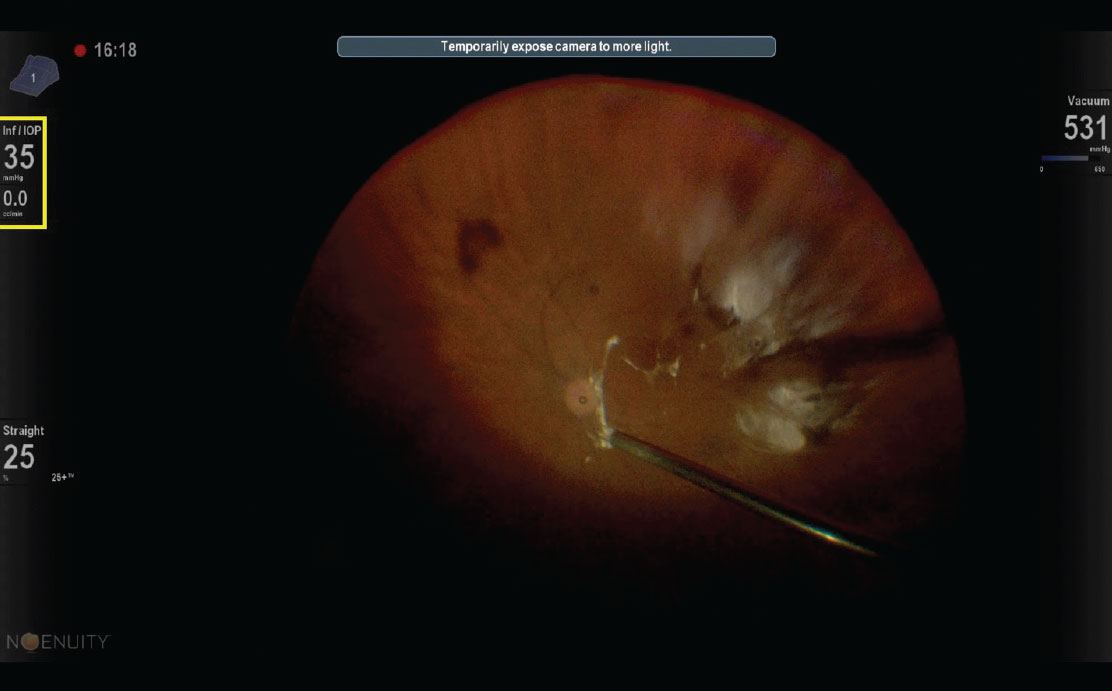

A view of a posterior vitreous detachment using a soft-tipped cannula and the Ngenuity heads-up display (Alcon). Note the upper left inset (yellow box) indicates a flow rate of 0.0 cc/min when the instrument is completely occluded by the posterior hyaloid. |

Visual cues on 3D heads-up display indicate occlusion

A built-in aid for PVD induction is to follow flow rates on the vitrectomy machine, taking advantage of the fact that the flow rate, often indicated adjacent to the set infusion pressure, will read near zero when the instrument is effectively occluded by the posterior hyaloid (Figure). This can be ascertained with an assistant giving verbal cues from a conventional display of any of the available vitrectomy platforms.

Alternatively, you can directly view the flow rate on a three-dimensional heads-up display (e.g., Ngenuity, Alcon). In inducing a PVD, when the flow rate drops to zero upon aspiration, simply remain in place while maintaining strong suction with the instrument port occluded for another two to three seconds; then elevation can begin.